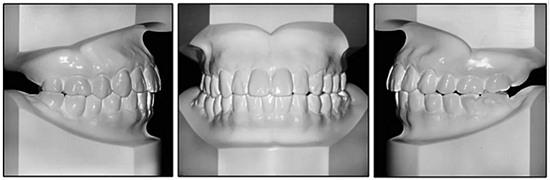

36歲;女性;尋求下頜左后方區(qū)域間隙管理的建議(圖1和圖2),通過治療獲得了良好的牙頜面效果(圖3和圖4)。她被診斷患有骨性I類和代償性牙性II類錯合畸形,并且上頜左側(cè)尖牙缺失(圖1和2)。大約七年前,由于不可修復(fù)的齲齒,拔除了下頜左側(cè)第一和第二磨牙(圖5)。37相鄰的第三磨牙向近中移動并傾斜入間隙,導致無牙頜間隙減小至約14 mm(圖2和圖5)。臨床和影像學評估顯示多發(fā)性齲損和在下頜右側(cè)567處有一不良的固定橋修復(fù)體(圖1和5)。此外,下頜左中切牙缺失,造成下頜中線向左側(cè)偏移約3 mm(圖1和圖2)?;颊咦栽V,她的右上第一前磨牙和左上尖牙在13歲時由其家庭牙醫(yī)拔除,因為它們被阻塞到頰側(cè)萌出(圖1)。上頜第二磨牙缺失(未知病因),并且相鄰的第三磨牙已經(jīng)轉(zhuǎn)移到第二磨牙間隙中。如補充材料所示,美國正畸學差異指數(shù)DI是28分。種植體部位(下頜左側(cè)和右側(cè)第一磨牙)由于復(fù)雜性得到額外4分(補充材料)。

圖2. 治療前牙齒模型